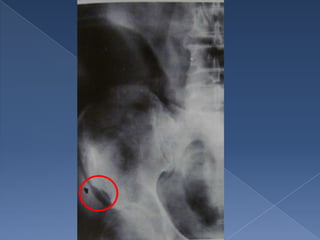

20% de lospolipos de colon derecho no son vistos en coloscpias La coloscopia causa sangrado en 2% El enema opaco de doble contraste permite ver 90% de los polipos

• 7.

Es dificil diferenciar entre maligno Imagen en y beningno manzana cuando miden mordida 1 cm o menos los polipos El tumor Coloscopia crece y enema no periluminal y determinan causando estadio estrechez